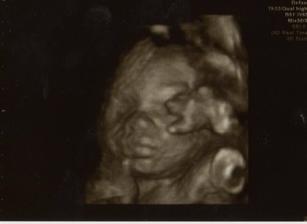

2.3.2010, 22+4tt - 3D UTZ